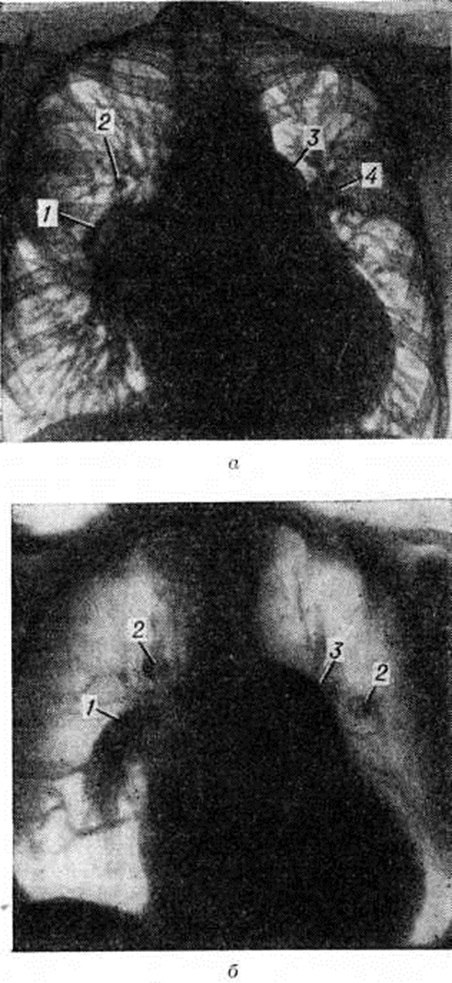

При рентгеноскопии и рентгенографии при выраженной прекапиллярной Гипертензия малого круга кровообращения определяется расширение лёгочного ствола, лёгочных артерий и их сегментарных ветвей (рисунок 6, а), а также выраженная гипертрофия правого желудочка сердца и особенно пути оттока крови. В периферических отделах лёгочных полей сосудистый рисунок обеднён, лёгочные вены сужены. При посткапиллярной Гипертензия малого круга кровообращения отмечается расширение как артерий, так и вен лёгких.

С помощью томографии (рисунок 6, а) возможно дифференцированное изучение лёгочных артерий и вен. По соотношению артериальных и венозных сосудов лёгкого можно выделить три типа изменений: 1) вены расширены, артерии имеют нормальный или незначительно увеличенный калибр — картина, характерная для лёгочной гипертензии при левожелудочковой недостаточности, панцирном сердце и митральном пороке (посткапиллярная Гипертензия малого круга кровообращения); 2) артерии и вены расширены — наблюдается, как правило, при врождённых пороках сердца (смешанная форма Гипертензия малого круга кровообращения); 3) крупные ветви лёгочной артерии расширены, а периферические ветви и лёгочные вены сужены — характерно для выраженной стадии первичной лёгочной гипертензии, комплекса Эйзенменгера, лёгочного сердца (прекапиллярная Гипертензия малого круга кровообращения).

Рентгеноконтрастное исследование сосудов лёгких (ангиокардиопульмонография) выявляет резкое расширение лёгочного ствола, лёгочных артерий и их сегментарных ветвей (рисунок 8). Мелкие артериальные сосуды имеют вид грубых тяжей, отсутствуют древовидные ветвления, в паренхиматозной фазе отмечается неоднородное понижение прозрачности, а венозная фаза определяется нечётко.